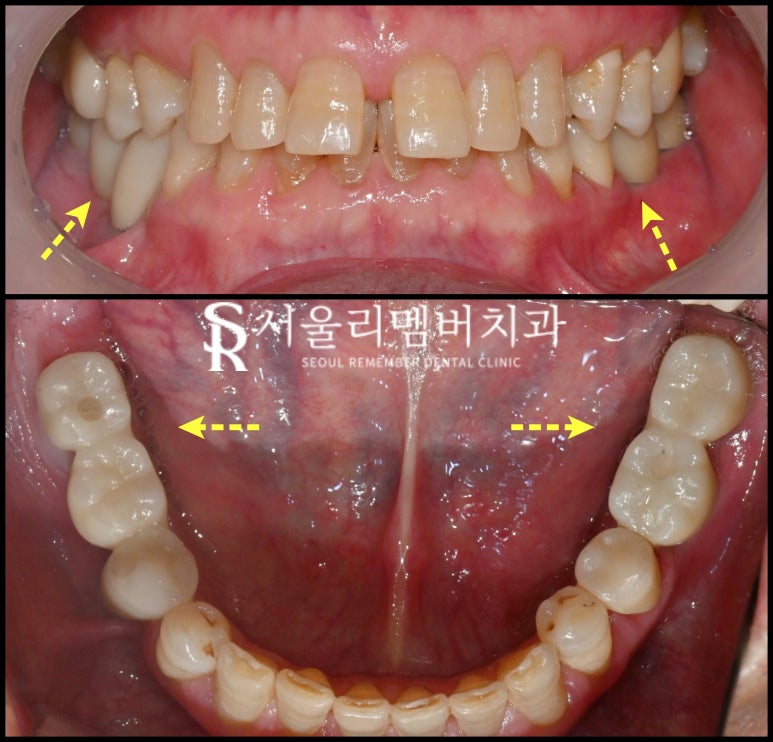

일단 정확한 진단을 위해

구강 카메라로 찍어봤습니다.

곳곳에 있는 치석과 퇴축된 잇몸을 보아

확실히 관리가 안 된 상태를 볼 수 있는데요.

원래 있던 보철을 제거하고

식립 및 신경치료를 진행했는데요.